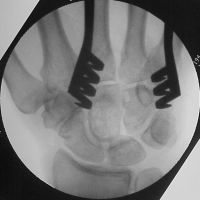

| and then after the

defect was filled with corticocancellous iliac crest

bone graft to improve structural stability: |

| Pressure fit bone

graft in place. |